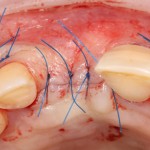

Другой вариант. Имплантируем, но существующего объема костной ткани недостаточно для получения адекватного эстетического и функционального результата:

Поэтому мы используем мембрану Geistlich BioGide и всё ту же аутокостную стружку:

Вот чем мне нравится мембрана BioGide — так это своими свойствами. Предсказуема до мелочей.

Во влажном состоянии она эластична и податлива, поэтому нет необходимости использовать пины или винты:

ну и, швы: